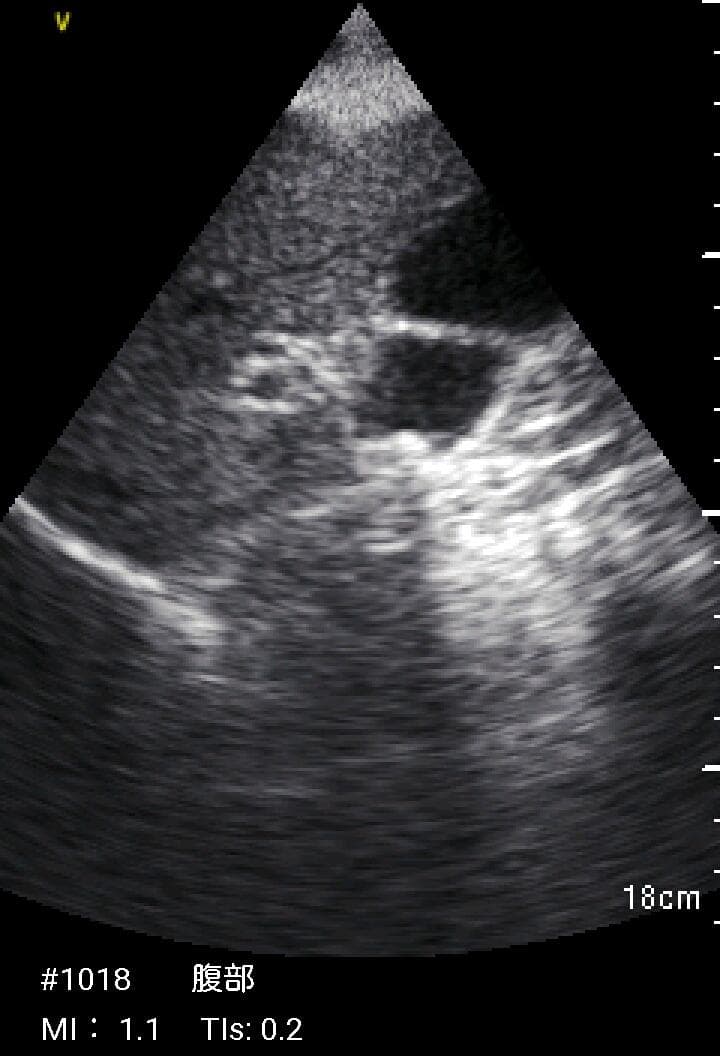

おわかりになる方のみの購入をお願いいたします実際に実施した写真をあげました正常肝臓、胆石症、頸動脈プラーク、同じく頸動脈プラーク、Mrの収縮期、同じくM弁の開放期とA弁の開放期、腹部大動脈瘤、正常の頸動脈、甲状腺右葉の結節、前立腺肥大画像の描出は条件によりますがご検討をお願いいたします経年変化、使用に伴うスレや傷などがあります機能に問題はありませんスキャンは心血管、腹部、体表に対応します外部接続端子のカバーが一部壊れていますが蓋は閉まりますバッテリーはフル充電されますが劣化はあると思います医療用モニタリング機器 Vscan Extend、GE- モデル名: Vscan Extend- ブランド: GE- 色: ホワイト- 機能: 医療用モニタリング機器ご覧いただきありがとうございます。鈴木 ALCARE Youcare-TDc 医療用テープ 25mm 6個。